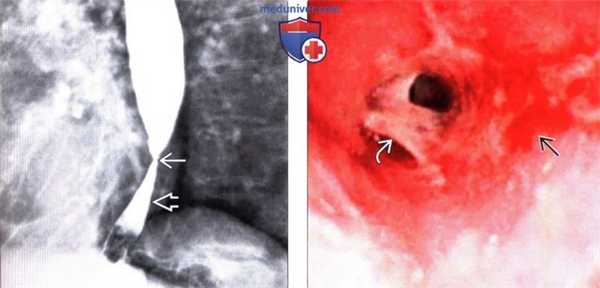

Рефлюкс-эзофагит с сегментарным сужением просвета у мужчины 50 лет.

В дистальном отделе пищевода выявлено сегментарное сужение с ровными контурами без повреждений слизистой оболочки (без изъязвлений) (указатели).

Такие проявления более характерны для рефлюкс-эзофагита, чем для опухоли. Рефлюкс-эзофагит с сегментарным сужением просвета у мужчины 50 лет.

Такие проявления более характерны для рефлюкс-эзофагита, чем для опухоли. Рефлюкс-эзофагит с фокальной стриктурой у женщины 63 лет.

(а) Выявлены фокальная стриктура (стрелка) в дистальном отделе пищевода и расширение проксимального отдела с утолщением складок (указатели).

(б) При рентгенографии с двойным контрастированием четко визуализирована фокальная стриктура пищевода (стрелка).